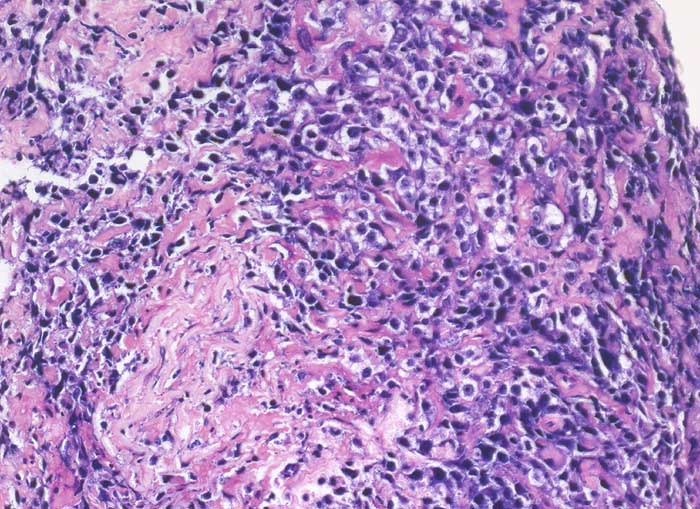

Diffuse grosszellige B-Zell Lymphome treten nicht selten in extranodalen Lokalisationen auf und können klinisch als Karzinom fehlgedeutet werden. Bei ungewöhnlicher Zytomorphologie eines malignen Tumors sollte deshalb immer auch an die Möglichkeit eines nicht epithelialen Tumors gedacht und der Befund mittels Immunzytochemie weiter abgeklärt werden. Zur Unterscheidung eines Lymphoms von einem epithelialen Tumor eignen sich der panleukozytäre Marker CD45 (LCA) und ein Panzytokeratinmarker oder BerEP4.

Beim ersten Fall handelt es sich um ein primär extranodales Lymphom des Nierenbeckens, das im Urin diagnostiziert wurde. Beim zweiten Fall handelt es sich um ein primär extranodales Lymphom im Bereich der Nebenniere mit Nachweis von Lymphomzellen im Aszites.